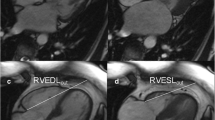

Based on the methodology described above, two methods were used for determining RV volumes, function and mass. With method 1 trabeculae and papillary muscles were included in the blood volume. With method 2, trabeculae and papillary muscles were excluded from the blood volume (Fig. 1) and added to the myocardial volume. For both methods the volume between the endo- and epi-cardial contour was considered myocardial volume. Selection of trabeculae and papillary muscles was done using semi-automatic pixel-intensity based segmentation software. The segmentation software is based on the signal intensity distribution of MR images and has been described in detail by Freling et al. [16]. In brief, voxels within the epicardial contour are classified as either blood volume or myocardial volume according to their signal intensity, taking into account spatial variations in signal intensity. Based on this algorithm, trabeculae and papilary muscles were excluded from the blood volume and included in the myocardial volume. The algorithm works similar for images generated by the different scanners used in this study. It was a possibility to manually change the threshold for every slice, in order to select the same trabeculae in end-diastole and end-systole. Observers selected only trabeculae with signal intensity similar to the intensity of RV myocardium. Individual voxels could also be selected or deselected in case of artifacts due to nonlaminar flow.

RV contour tracing only (A-1 and B-1) and with semi-automatic selection of trabeculae (A-2 and B-2). Two methods of measuring RV volumes in a healthy control (a) and patient after atrial switch procedure (b). Method 1: inclusion trabeculae in the blood volume (a-1 and b-1); Method 2: exclusion of trabeculae from the blood volume, using identical endocardial contours (a-2 and b-2)